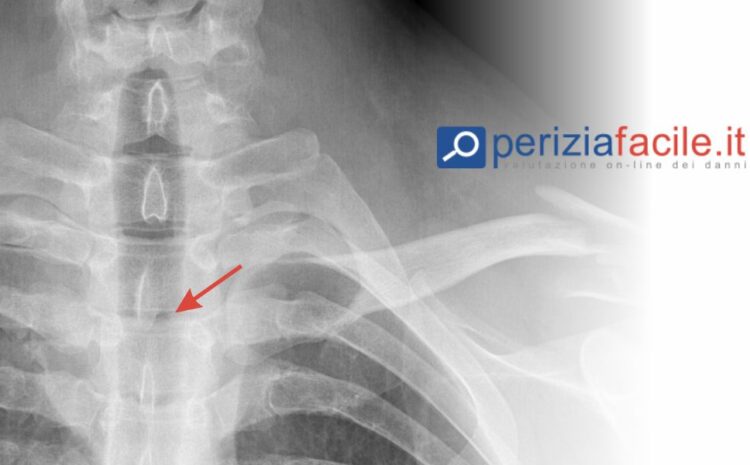

Quanto viene valutato un infortunio con frattura vertebre?

Se hai subito la frattura di due vertebre, ad esempio, si tratta probabilmente di una lesione grave e probabilmente sarete assenti dal lavoro per almeno tre mesi.

Una frattura di questo tipo può causare problemi a lungo termine, come dolori alla parte bassa della schiena e spasmi che possono impedire di svolgere determinate attività, come sollevare carichi pesanti o piegarsi.

I fattori principali sono: la gravità della lesione, compresa l’entità di eventuali danni permanenti, e l’eventuale paralisi o dolore costante.